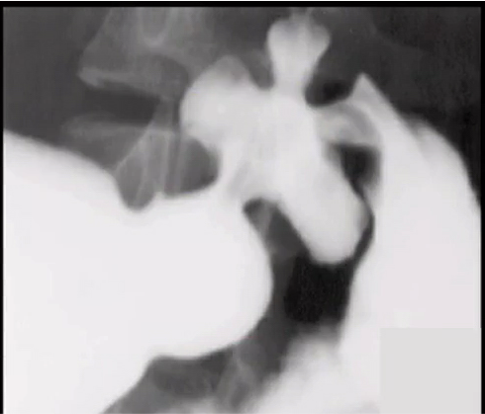

Features suggesting benign gastric ulcer

NOTE: Remember Hampton’s (Harmless = benign) and Carman (Carcinoma = malignant)

Features suggesting a malignant gastric ulcer

benign or malignant?

benign